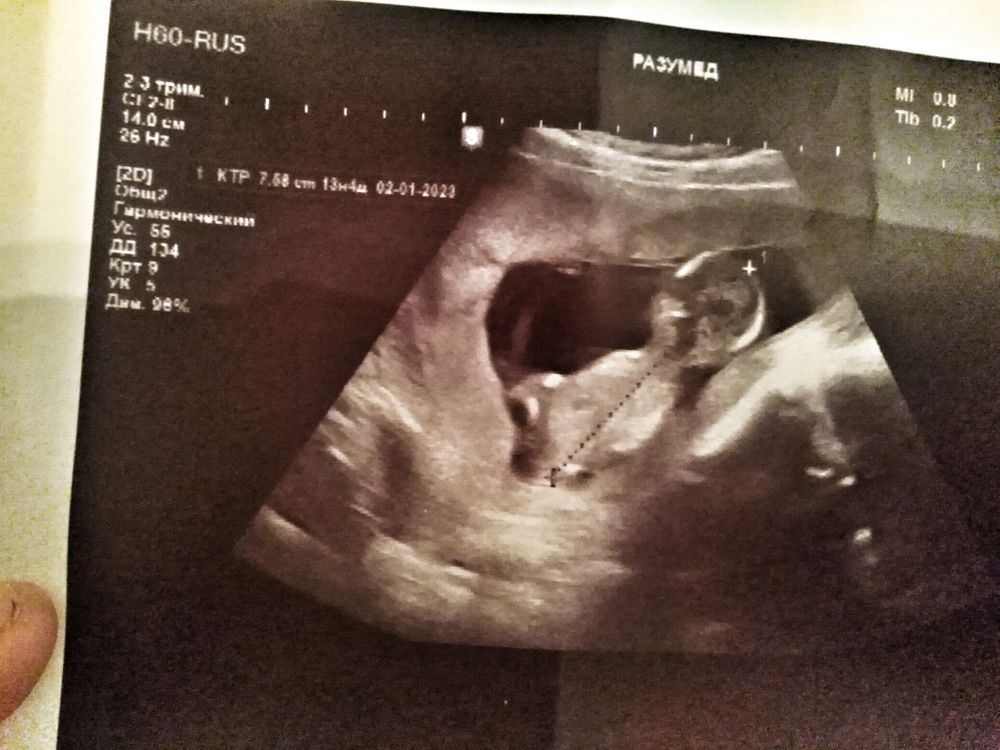

Скрининг 1, пол может можно распознать? Смахивает мб? 🤗

Девочки не ругайтесь на меня😄14 неделек.просто очень интересно ведь, 1 бер все таки)))

наверно не понятно тут не очень видно, да и срок ещё не такой чтоб увидеть наверно

Но я не разбираюсь в этом, может тут все таки можно рассмотреть на кого похож там например?)) 🤗 кувыркался там конечно за секунды в разные просто позы и так и так 😄